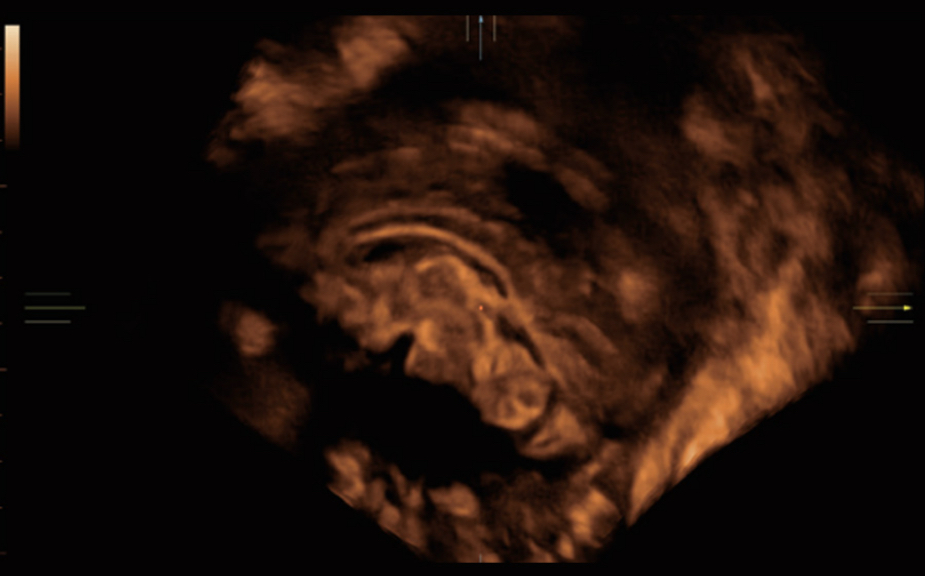

Nuewa I9, kad?nlara ve yenido?anlara y?nelik sa?l?k hizmetleri i?in ?zel olarak tasarlam??t?r ve i?ten d??a yenilik?i bir deneyim sunmaktad?r. Bu yenilikler, karma??k klinik senaryolara ili?kin derinlemesine bilgilere dayal? olarak geli?tirilmi?tir ayr?ca do?ru ve zaman?nda yan?tlar?n yan? s?ra, ola?an├╝st├╝ verimlilik ve ola?an├╝st├╝ kullan?c? deneyimi sunar.

ZST + Taraf?ndan Desteklenen Eksiksiz ??z├╝m

ZST+ platformu, ultrason evrimini temsil eden ola?an├╝st├╝ bir yeniliktir. Ultrason ?l?├╝mlerini geleneksel ???n bi?imlendirmeden kanal verilerine dayal? i?lemeye d?n├╝?t├╝r├╝r. Mekansal ??z├╝n├╝rl├╝k, zamansal ??z├╝n├╝rl├╝k ve doku homojenli?i aras?ndaki geleneksel dengeli s?n?rlaman?n ├╝stesinden gelir ve kesintisiz iyile?tirmelerle s?n?rs?z g?r├╝nt├╝leme ??z├╝mleri i?in ola?an├╝st├╝ g?r├╝nt├╝ kalitesi sunar.